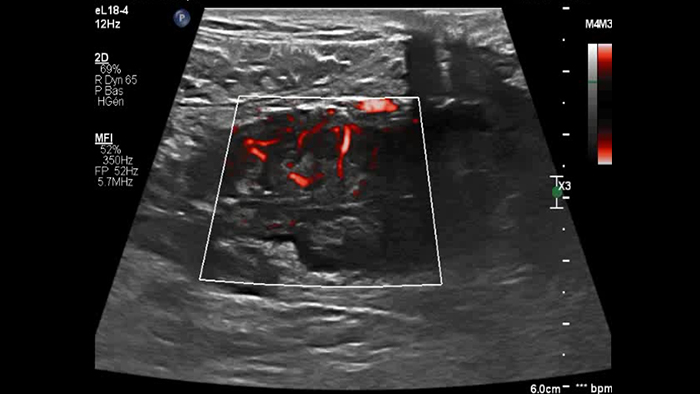

Ces images précises des lésions des couches pariétales forment la base de l’interprétation des changements induits par l’inflammation des parois intestinales et par conséquent de la différenciation entre la maladie de Crohn et la rectocolite hémorragique. L’exploration avec la technologie MFI (MicroFlow Imaging) constitue la deuxième étape. Il s’agit de reconnaître l’aspect de l’hypervascularisation induite par des épisodes inflammatoires actifs. La paroi intestinale normale semble comporter peu de microvaisseaux détectables, uniquement à l’interface de la muqueuse et de la sous-muqueuse, et dans le tissu adipeux mésentérique adjacent. Inversement, la paroi inflammatoire présente de nombreux microvaisseaux. La distinction entre les images d’artefacts de mouvement et les microvaisseaux circulants est alors un point essentiel nécessitant un ajustement parfait des paramètres de détection des micro-flux (voir les boucles, diapositive 8). La comparaison des 4 images suivantes de la maladie de Crohn met en évidence des différences claires qui devraient être interprétées comme étant représentatives des différents états inflammatoires. L’image 1 ne comporte aucun vaisseau visible, ce qui correspond probablement à une absence d’activité. L’image 2 présente quelques vaisseaux ; nous pouvons en conclure que cela correspond à une activité modérée. L’image 3 comporte un plus grand nombre de vaisseaux, signe probable d’une activité intense. L’image 4 présente encore plus de vaisseaux de type pulsatile, ce qui évoque probablement une activité très intense.

Les images sont absolument différentes selon l’état inflammatoire. C’est une question de densité, de pulsatilité, mais également de localisation des vaisseaux. C’est l’avantage de la superposition des images de micro-flux à celles des couches pariétales obtenues par échographie haute résolution. Sur les images suivantes, accompagnées des clichés d’IRM correspondants, il semble que dans le premier cas, à savoir une maladie de Crohn d’apparition récente, les vaisseaux soient localisés à la surface de la paroi intestinale, probablement au niveau de la muqueuse. En revanche, dans les autres cas de maladie plus avancée, ils sont également plus visibles à l’intérieur de la sous-muqueuse et dans le tissu adipeux adjacent.

Dans cette forme tardive et probablement fibreuse de la maladie de Crohn, la sous-muqueuse comporte peu de microvaisseaux, tandis que l’ensemble de la paroi intestinale enflammée adjacente à la fistule présente une micro-vascularisation intense.